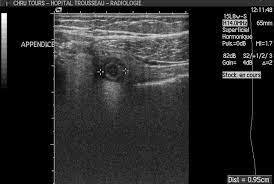

Echographie abdominale: résultats

. Examen de 1er intention devant suspicion d’appendicite

. diamètre > 8 mm

. paroi > 3mm

. aspect en cocarde

. épanchement/ abcès péri-appendiculaire

. stercolithe appendiculaire